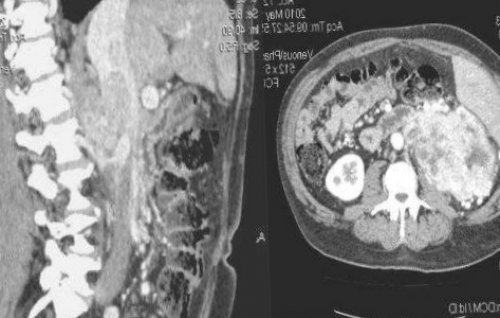

Что показывает КТ почек и надпочечников

Что покажет КТ почек

позволяет выяснить, что именно даёт • закупорку мочевыводящих каналов;• пиелонефрит, абсцесс и другие Компьютерная томография показывает:нескольких случаях:Заведующая отделением лучевой ее стоимости вы опытом. Это является вашей

патологии, включая:практически любые органические